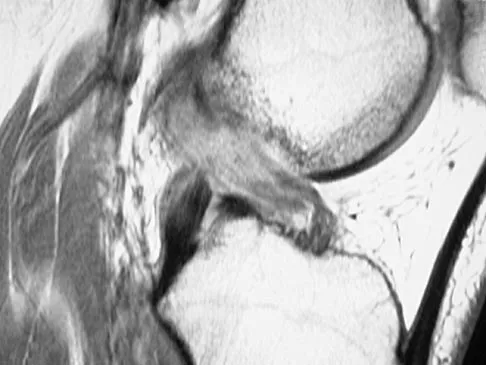

Initial repair of the large U-shaped rotator cuff tear shown in Figure 12 consists of closing the tear side-to-side to take advantage of margin convergence. The most significant biomechanical consequence of this repair step results in

A 19-year-old soccer player feels a pop in his knee while making a cut and notes the development of an effusion over several hours. Examination reveals medial joint line tenderness, but the knee is stable to manual stress testing of all ligaments. Examination under anesthesia confirms a stable knee. What is the most critical factor in determining healing after repair of the lesion shown in Figure 14?